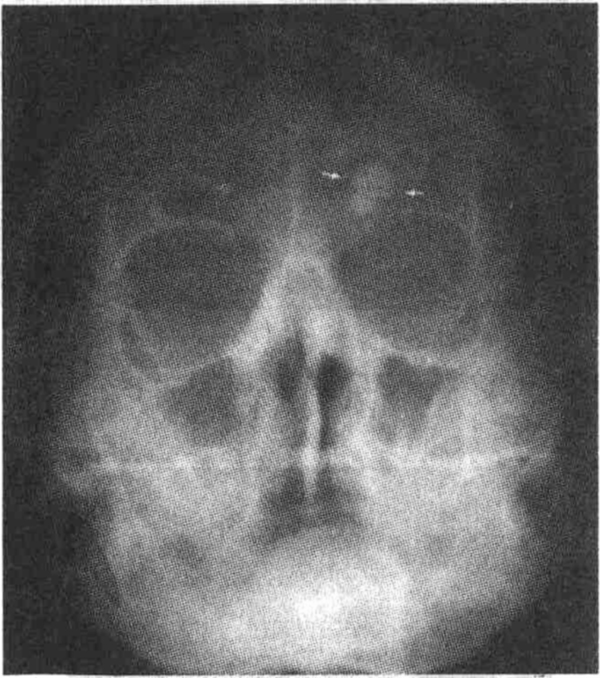

3. У 30-летнего мужчины с ректальным кровотечением выявлено на рентгенограмме черепа в левом фронтальном синусе хорошо очерченное округлое образование повышенной костной плотности. Определите заболевание.

head13-4.jpg

Остеома. Подобные опухоли обычно развиваются из области формирования мембра-нозной кости параназальных синусов, кости черепа и нижней челюсти. Новообразования гладкие, округлой формы и менее 1 см в диаметре. Хотя они не злокачественные, но могут сопровождаться симптоматикой, зависящей от места возникновения. Синдром Гарднера — это наследственное заболевание, характеризующееся следующей триадой: множественные остеомы, опухоли мягких тканей и полипы толстой кишки.